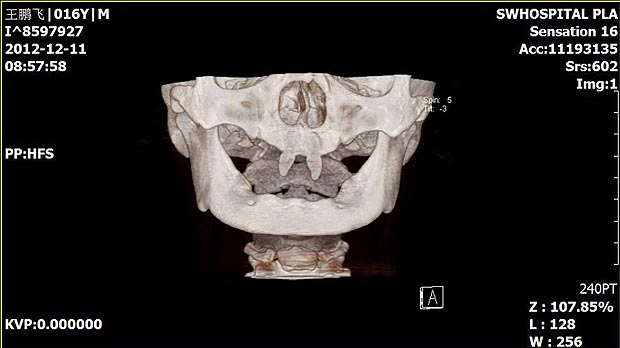

Վամպիրն ատամնաբուժարանում (լուսանկարներ)

16-ամյա մայրը Վանգ Պենգֆեյին բոլորը վամպիրի են նմանեցնում։ Տղան ընդամենը երկու սուր ժանիք ունի։

Պատանում մայրը՝ Վանգ Հույը, որդուն նախորդ շաբաթ նրան տարել է հիվանդանոց, որպեսզի պարզի այդ տարօրինակ երևույթի պատճառը և տղային նորմալի տեսքի բերեն։ Պատճառները պարզելու հարցում հույսեր կարծես չկան. բժիշկները դա համարում են բնական արատ։ Ինչ վերաբերում է այն շտկելուն, ապա դա հնարավոր է վիրահատության միջոցով։ Սակայն բժիշկները վիրահատությունը կկատարվի այն ժամանակ, երբ տղան չափահաս կդառնա։